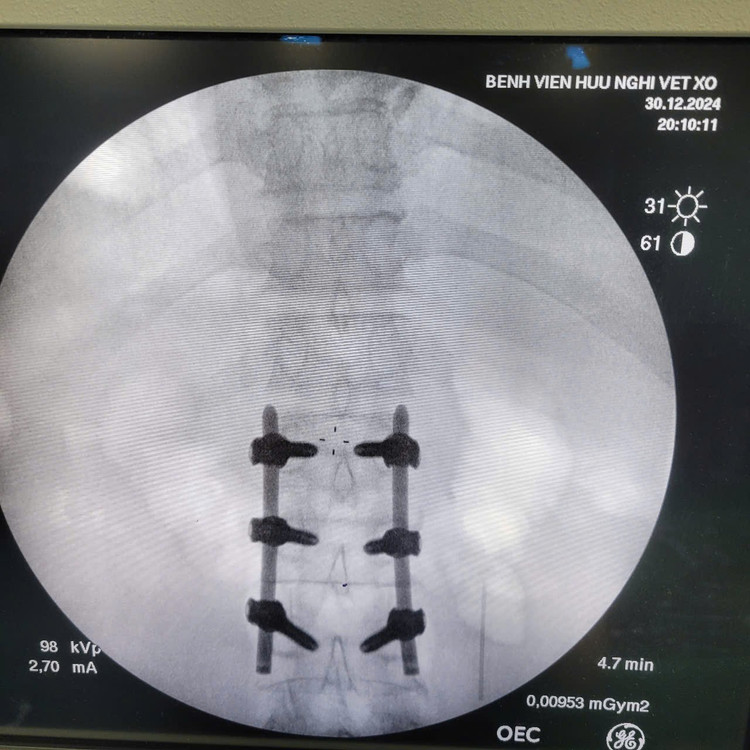

bat-vit-2.jpg

Bắt vít cột sống qua da.